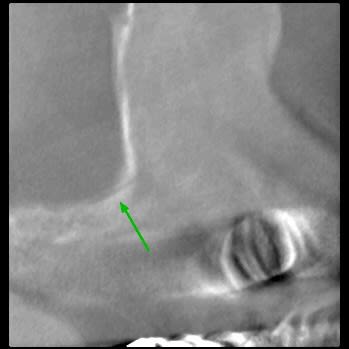

Je souhaite réaliser un sinus lift avec la pose de 2 implants en 15 et 16.

Mais sur le scanner je note la présence de l'artère alvéolo antrale intra osseuse, son trajet passe sur le site de mon futur volet.

1) ton artère est très basse, tu peux faire ton volet au dessus.

2) ton artère est toute petite et pas vraiment intra osseuse.

ici, comme signalé par CLIO, tu passes à l'aise par dessus.

Peu de risque pour l'artere alveolo-antrale.